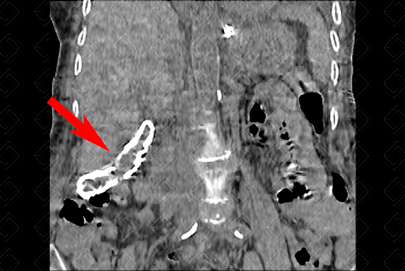

Texto alternativo para a imagem Figuras 1 e 2. Créditos: Dra. Elazir Mota - Rio de Janeiro/RJ

Descrição das figuras 1 e 2: Tomografia computadorizada de abdome evidenciando calcificação grosseira e concêntrica, envolvendo a parede da vesícula biliar (seta vermelha), caracterizando a clássica vesícula em porcelana.

• Radiografia convencional e tomografia computadorizada do abdome: As imagens são semelhantes, com a presença de halo de mineralização envolvendo a parede da vesícula biliar ( figuras acima );